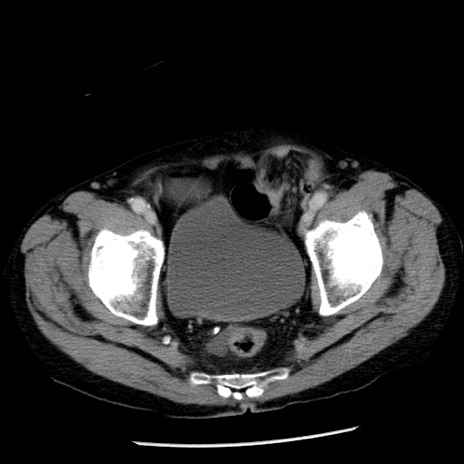

症例26(横断像)

【症例】80歳代男性

【主訴】嘔吐

【現病歴】昨晩2回嘔吐あり、今朝になっても嘔吐あり。来院。

【既往歴】胃潰瘍

【身体所見】意識清明、BT 37.6℃、BP 166/95mmHg、HR 100bpm、SpO2 97%、腹部:平坦・軟、腸蠕動音聴取良好、圧痛なし。

【データ】WBC 21900、CRP 1.46